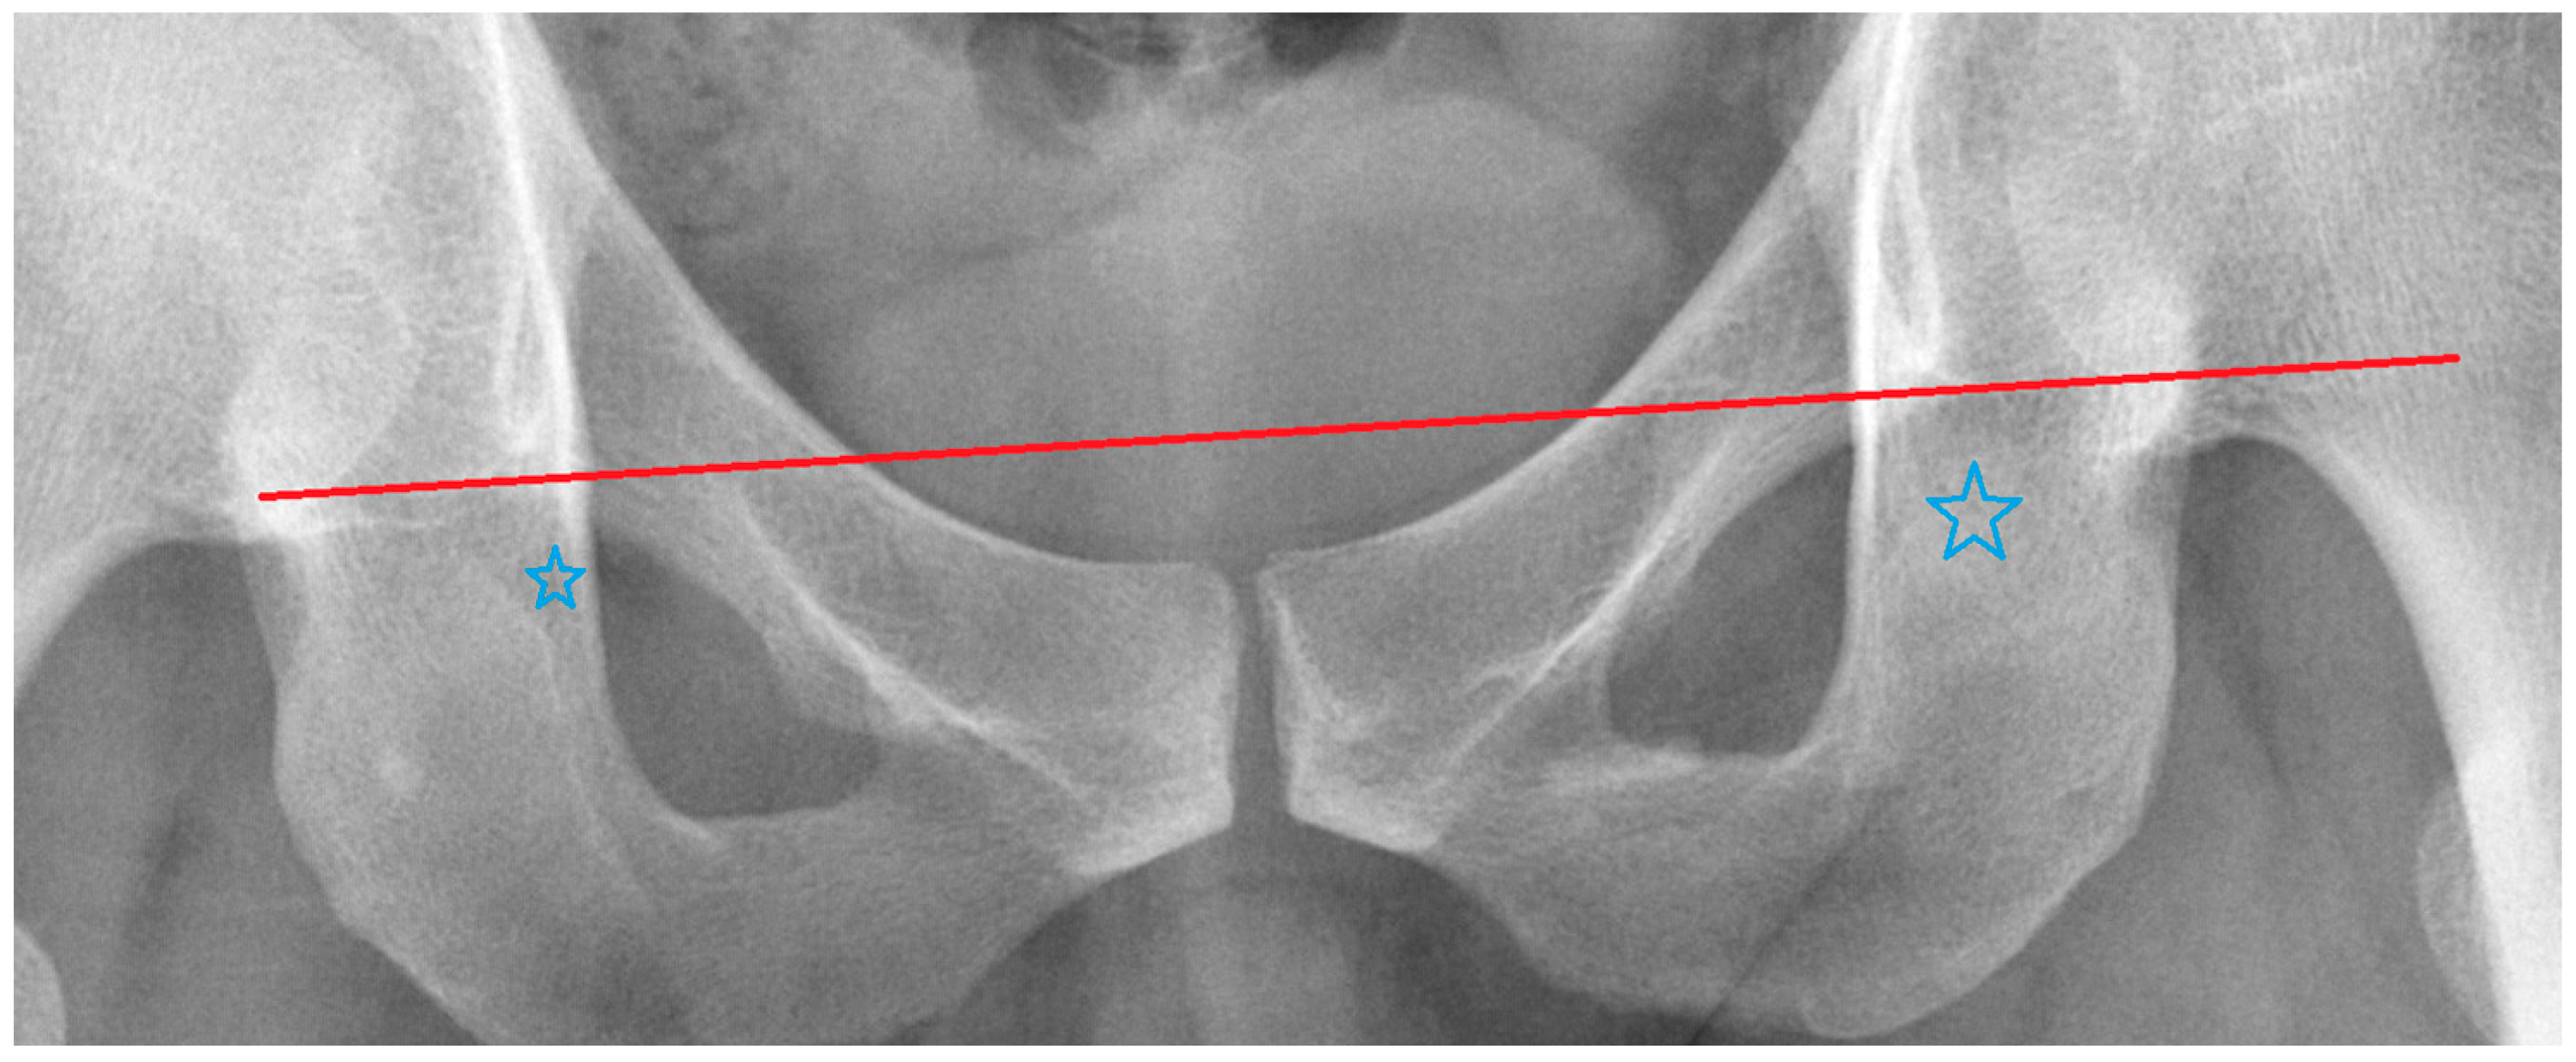

| The Outliers We Removed | Image Features |

|---|---|

| Outlier 1 of ∠RSC | Uneven protrusions on bilateral iliac crests. |

| Outlier 2 of ∠RSC | Normal |

| Outlier 1 of ∠RBI | Poor image quality, but borders of the pelvic landmarks are still visible. |

| Outlier 2 of ∠RBI | Right side femur fracture without femoral head dislocation. |

| Outlier 1 of ∠RIT | Asymmetrical teardrop shapes on both sides. |

| Outlier 2 of ∠RIT | Asymmetrical teardrop shapes on both sides. |

| Outlier 1 of ∠RUO | Normal |

| Outlier 2 of ∠RUO | The obturator foramen is slightly distorted on the image. |

| Outlier 1 of ∠RLO | Normal |

| Outlier 2 of ∠RLO | Normal |